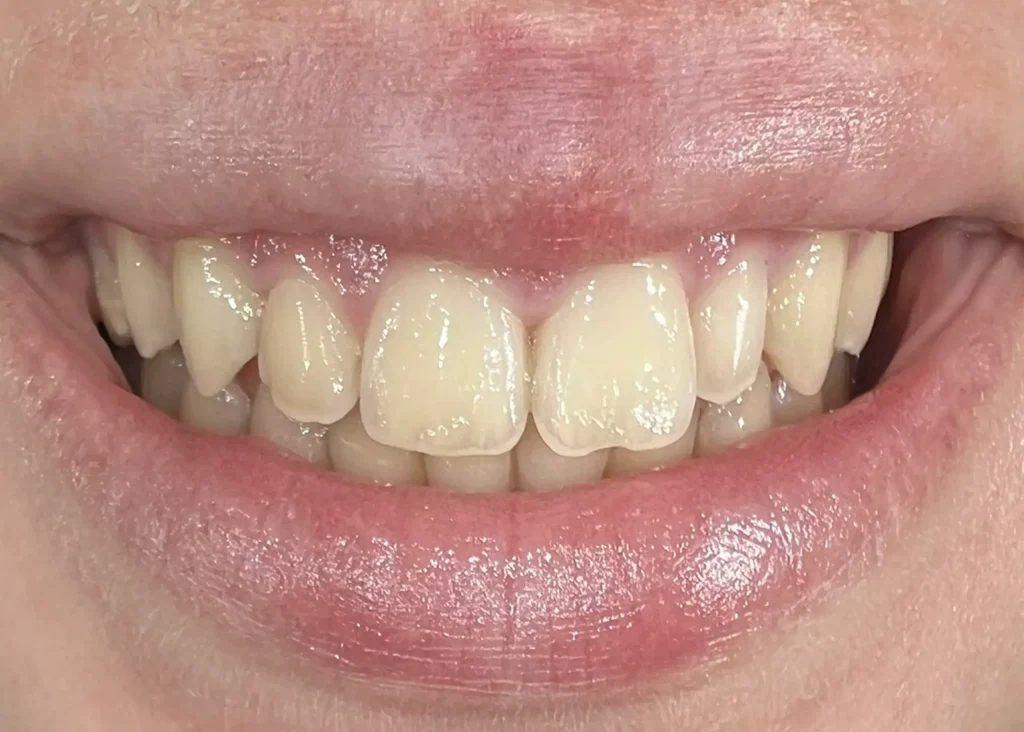

Casos clínicos de ortodoncia en CDPA